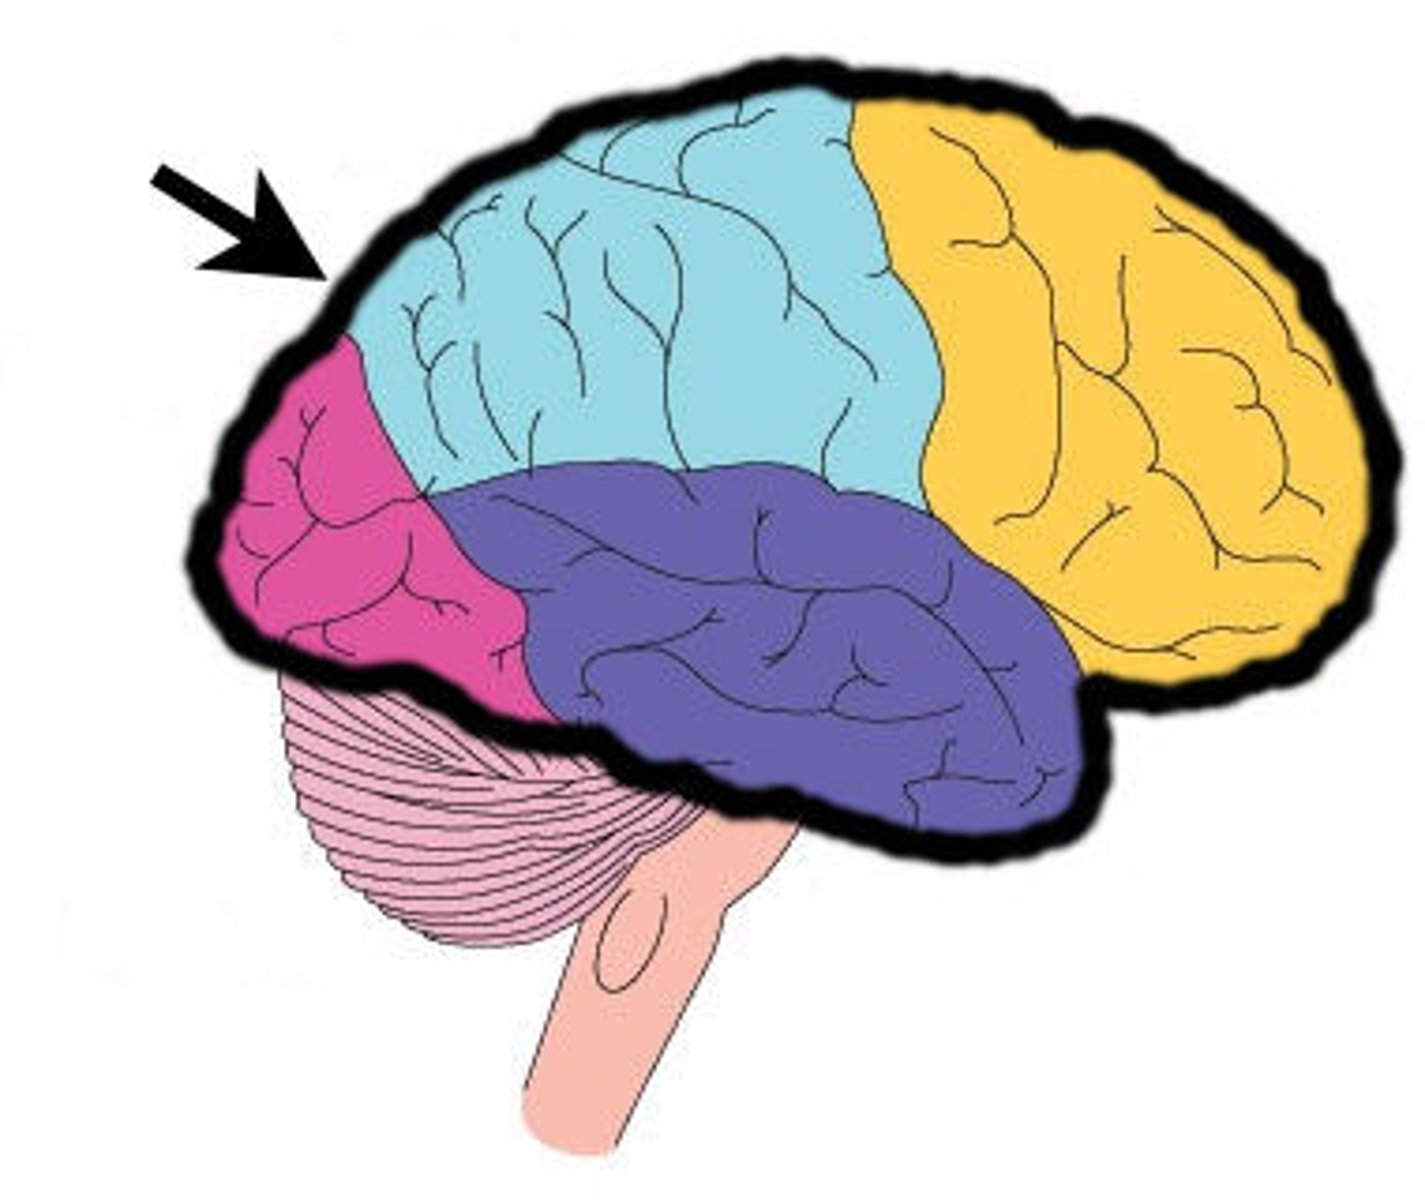

Lobes of the cerebrum

frontal, parietal, temporal, occipital

lateral cerebral sulcus

separates the frontal lobe from the temporal lobe

parieto-occipital sulcus

separates parietal and occipital lobes

cerebral cortex

specific types of sensory, motor, & integrative signals are processed in certain regions of the cerebral cortex.

sensory areas of cerebral cortex

Primary somatosensory, Primary visual, Primary auditory, primary olfactory, primary gustatory

motor areas of cerebral cortex

voluntary muscle movements

primary motor cortex

located in the frontal lobe; is the key motor control center responsible for initiating and coordinating movements

premotor cortex

located immediately anterior to the primary motor cortex, responsible for movements such as typing

integrative areas of the cortex

higher cognitive functions; association areas, prefrontal cortex, wernickle's area, broca's area

association areas of cerebral cortex

integrate diverse information

prefrontal cortex

part of frontal lobe responsible for thinking, planning, and language

Wernickle's area

language comprehension

broca's area

speech production